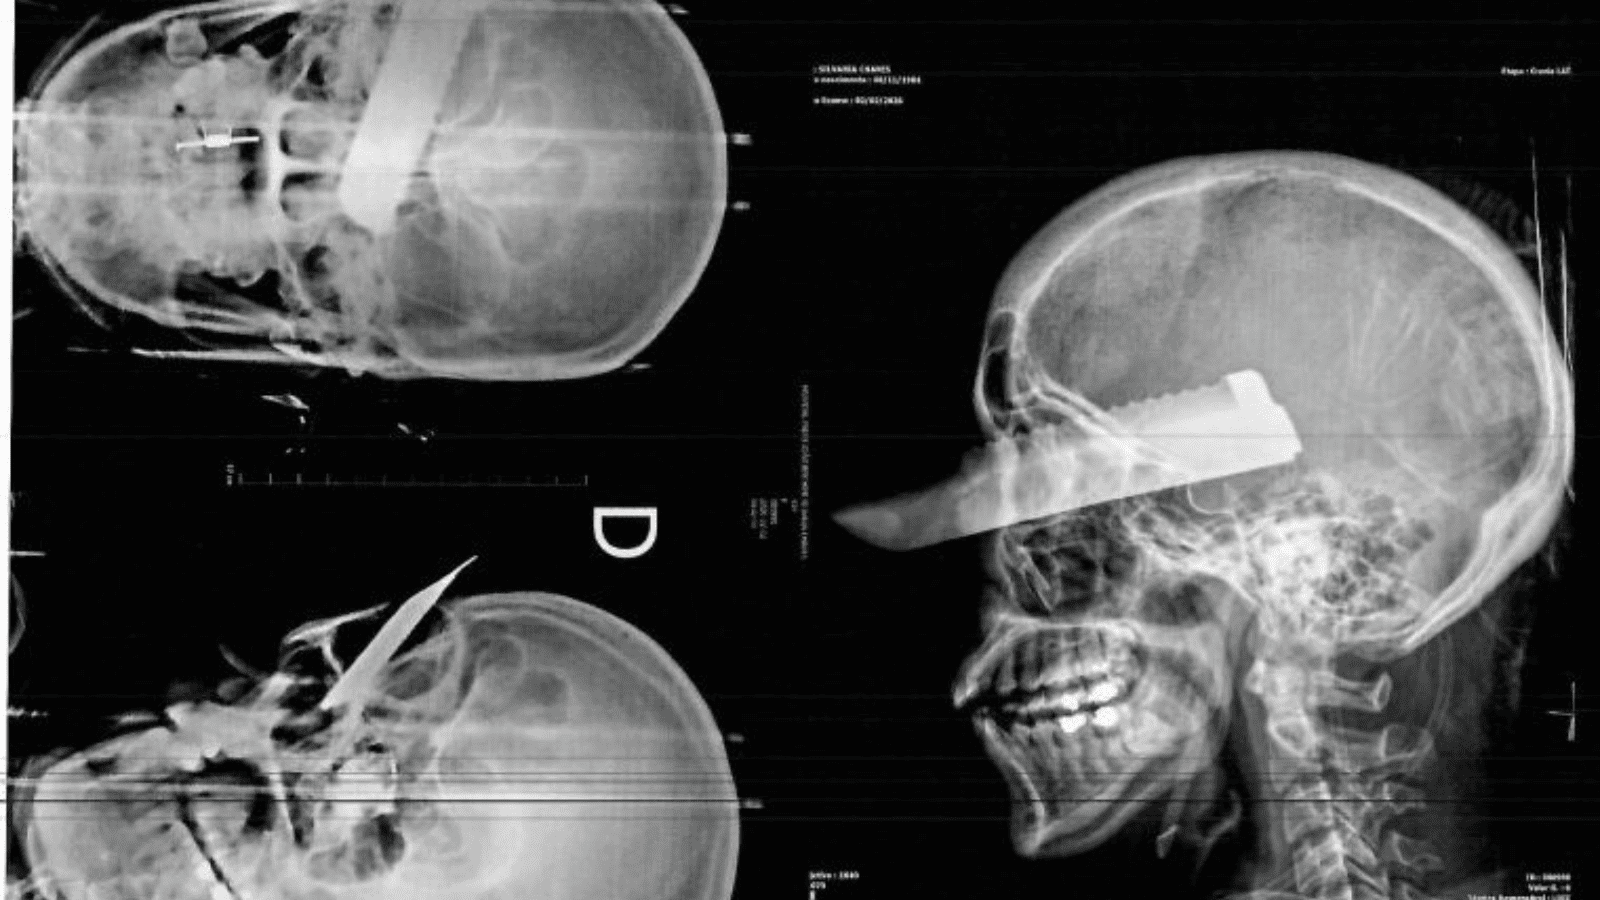

Sobrevivente de 41 anos caminhou para pedir socorro após ter crânio atravesado por faca

Conforme informações do Corpo de Bombeiros, a lâmina da faca atravessou o crânio da vítima e atingiu a região ocular. Todavia, a mulher demonstrou uma resistência surpreendente ao caminhar até a residência de vizinhos próximos para solicitar auxílio imediato.

Analogamente ao choque físico, a paciente apresentava hemorragia ativa e sinais claros de descompensação. Portanto, os paramédicos iniciaram os protocolos de estabilização ainda no local da ocorrência. Posteriormente, a equipe conduziu a vítima em estado crítico ao hospital da cidade.